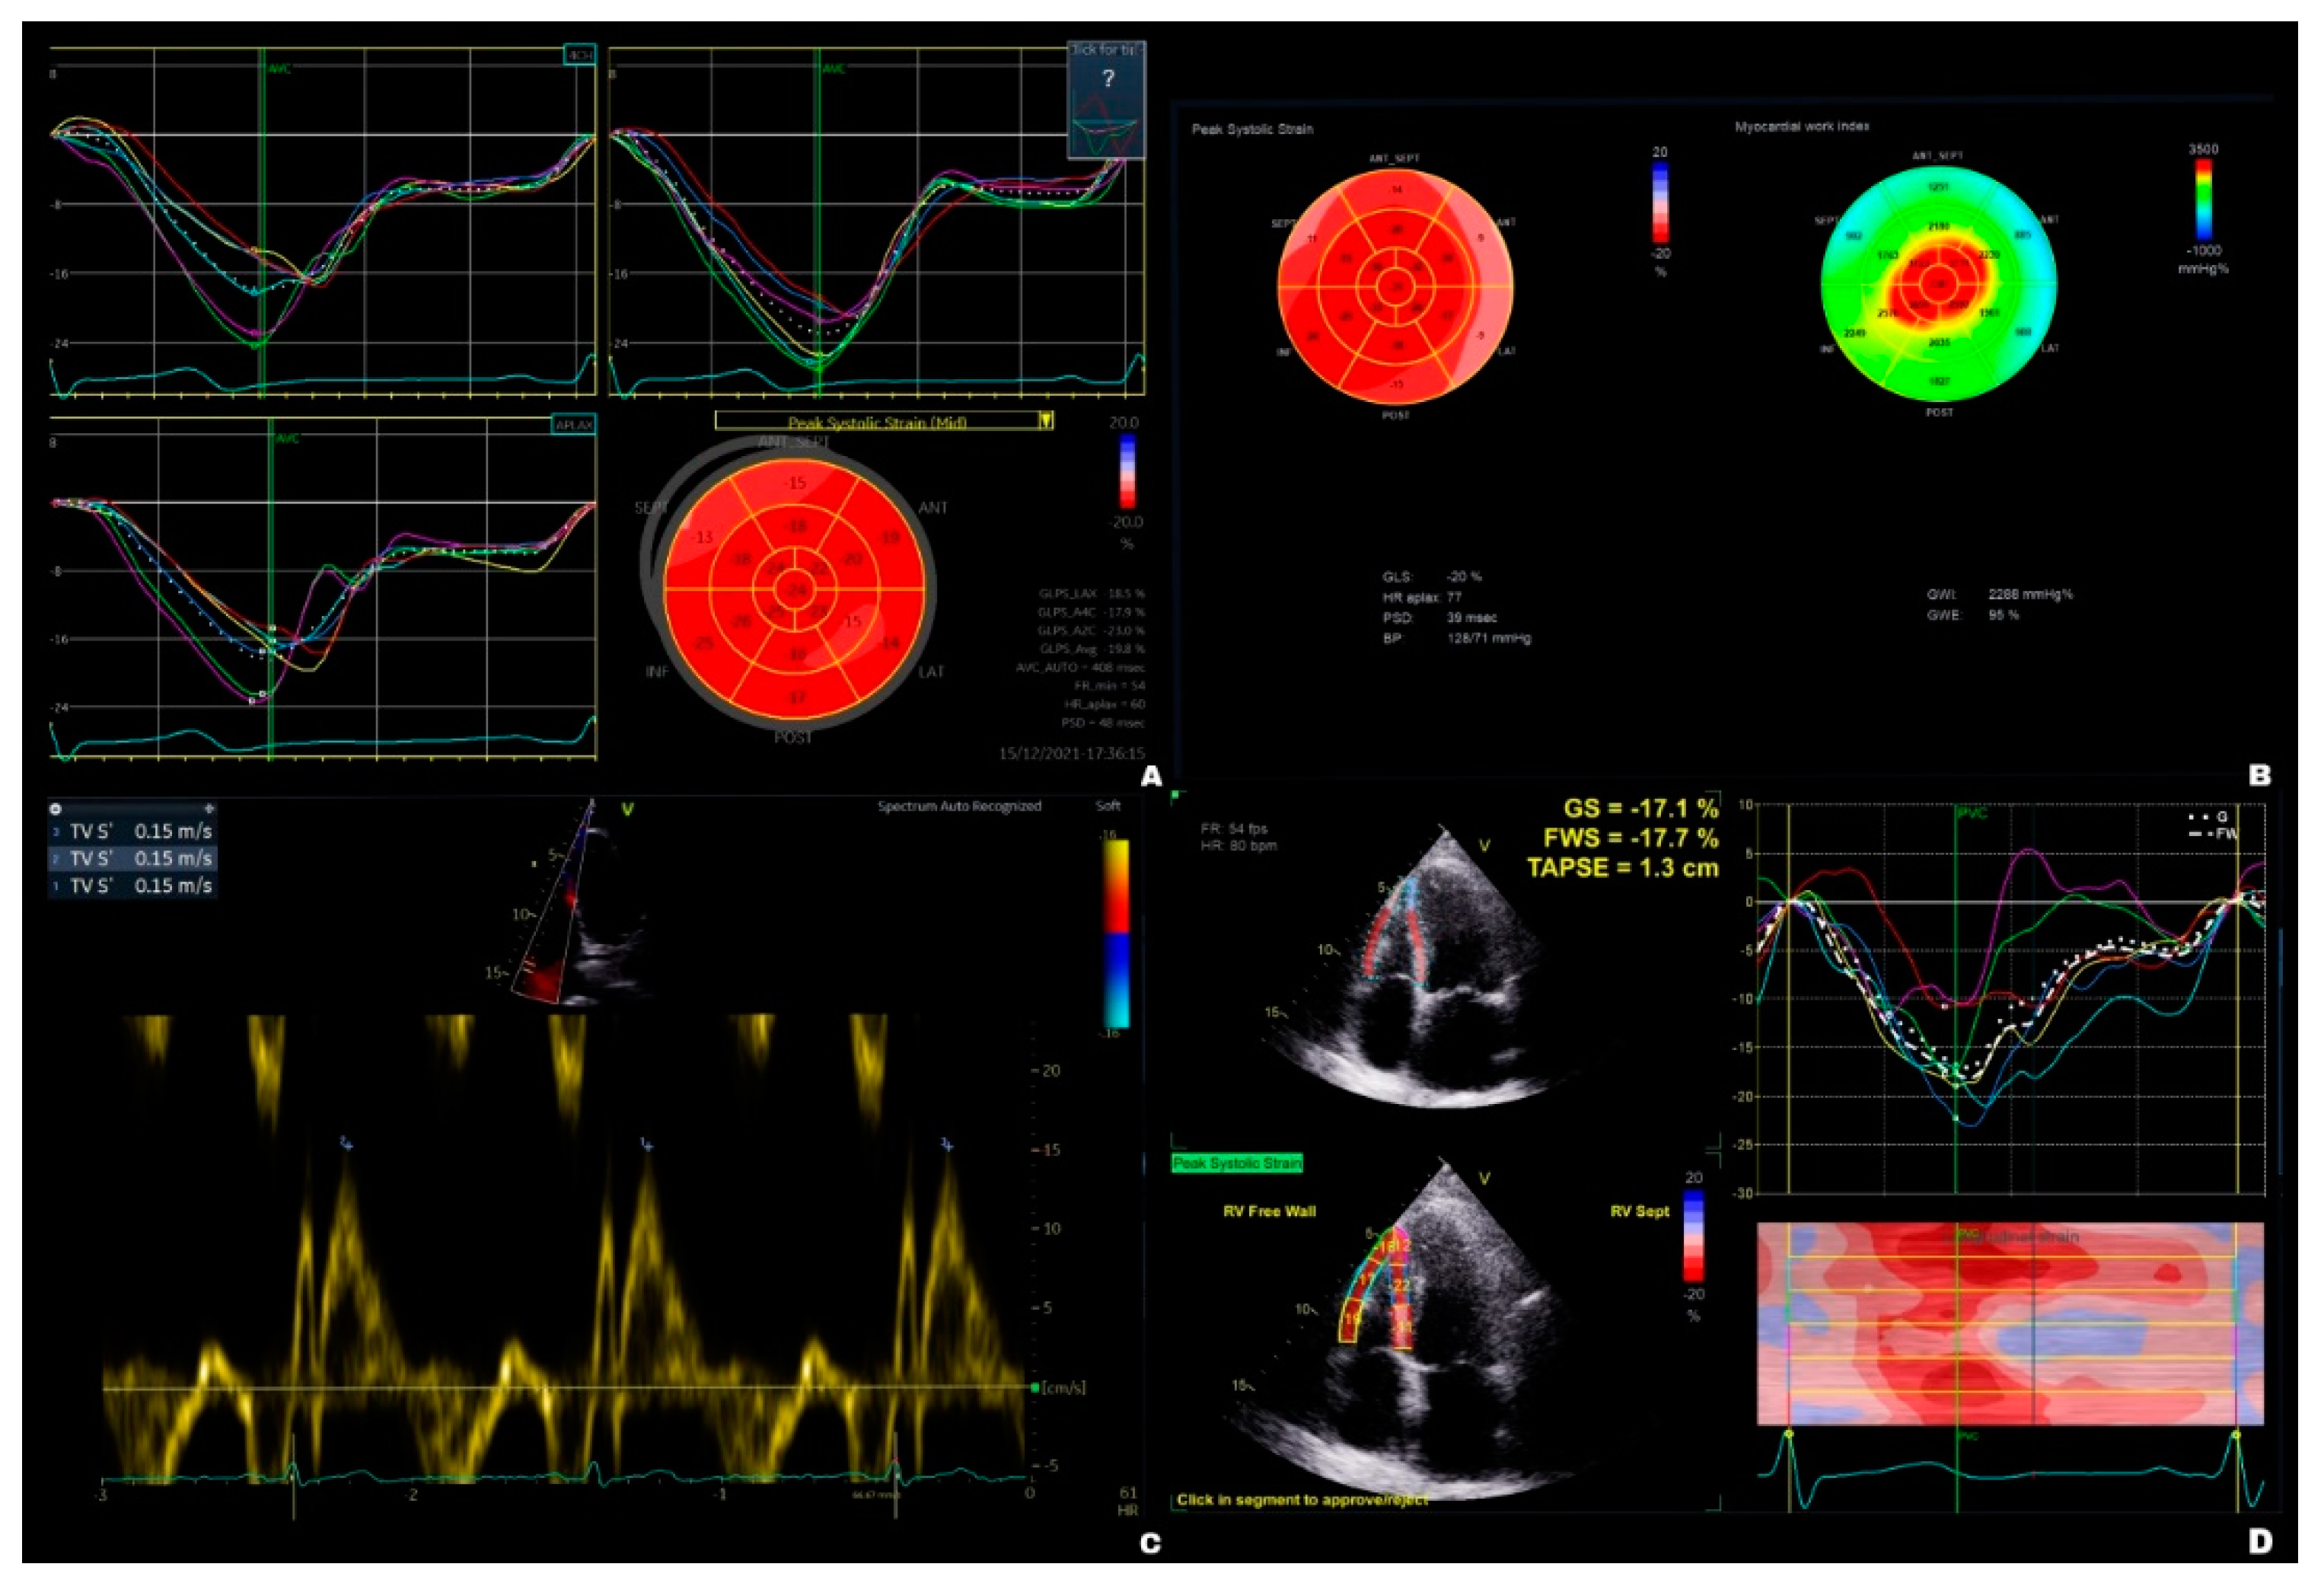

| GLSLV avg. (%) | -17.40 ± 4.14 | -16.7 ± 4.13 | 0.813 | -17.5 ± 2.78 | -16.10 ± 4.46 | 0.532 |

| GWILV | 1617 ± 529 | 1637 ± 462 | 0.997 | 1778 ± 580 | 1505 ± 636 | 0.074 |

| GWELV (%) | 90.90 ± 9.05 | 90.60 ± 7.56 | 0.991 | 93.20 ± 5.72 | 89.30 ± 10.70 | 0.068 |

| TAPSE (mm) | 20.80 ± 3.25 | 17.90 ± 3.83 | 0.005 | 20.60 ± 3.79 | 20.60 ± 3.51 | 1.000 |

| TASV (cm/s) | 13.90 ± 3.45 | 12.40 ± 2.86 | 0.184 | 14.10 ± 2.25 | 14.60 ± 2.54 | 0.874 |

| RV4CHGLS (%) | -16.80 ± 3.28 | -16.00 ± 4.46 | 0.911 | -16.70 ± 6.46 | -16.40 ± 4.91 | 0.992 |

| RVFWGLS (%) | -17.20 ± 9.07 | -11.50 ± 8.50 | 0.133 | -18.60 ± 10.30 | -17.50 ± 9.71 | 0.983 |